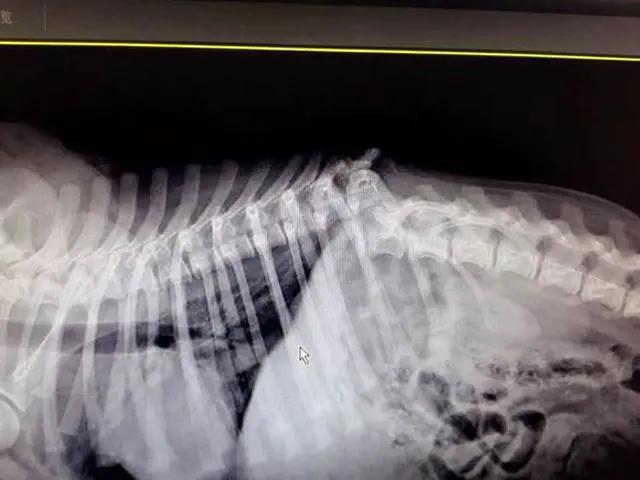

由于地区限制,这种手术属于大手术,当地做不了。去外地做的话,狗狗的身体条件也是不允许的。主人只想着能不能狗狗自己自愈,因为听说狗狗的生命力很顽强。

万幸的是,狗狗自我恢复的不错。可以自己坐起来,主人挠后腿也有反应。